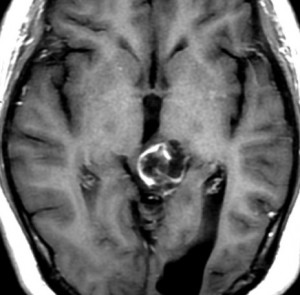

左はT1強調画像,右はFLAIR画像です。中脳視蓋が腫れて腫瘍がにじむように広がっているのがわかります。この腫瘍本体は15歳の時から21歳の時まで大きくなっていないので,中脳視蓋グリオーマ tectal gliomaの診断です。

T1強調ガドリニウム増強画像です。15歳の時は腫瘍の半分以上が強くガドリニウム増強されていましたが,この21歳の時の画像では,中心部やや右寄りに増強像が認められるだけです。この性質は,腫瘍が毛様細胞性星細胞腫であることを示しています。